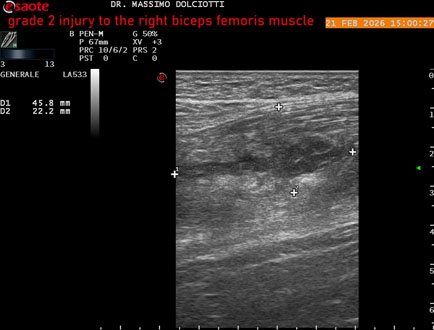

Ecografia del: 21/02/2026

Strumento: Esaote MyLab Eight

Sonda: Lineare Multifrequenza 3-13 MHz

Età Paziente: M 49 anni

Motivazione dell'esame: da 10 giorni dolore insorto durante la corsa.

Commento all'esame: le immagini ed il video documentano, al muscolo bicipite femorale destro, in sede prossimale, area disomogenea, ipoecogena, delle dimensioni di 27 x 24 mm (misura ottenuta per asse corto o trasversale) e delle dimensioni di 51 x 33 mm (misura ottenuta per asse lungo o longitudinale), da ricondurre a lesione muscolare di 2° grado con modica raccolta sieroematica intramuscolare.

Conclusioni: lesione di 2° grado al muscolo bicipite femorale destro (grade 2 injury to the right biceps femoris muscle).